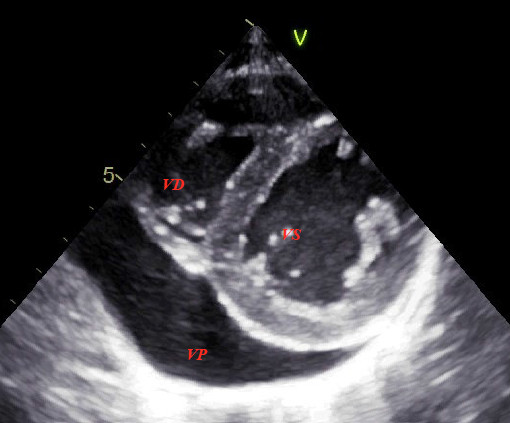

All’ecocardiografia viene evidenziato un versamento pericardico postero-mediale e anteriore al ventricolo destro dello spessore di 22 mm (Figura 1 e 2), in assenza di segni di interferenza emodinamica; la volumetria cardiaca, la funzione contrattile biventricolare globale e la flussimetria Doppler appaiono normali.

- Viene riportato il caso di una ragazza di 14 anni con disturbo della condotta alimentare (DCA) e con riscontro ecocardiografico di versamento pericardico dello spessore di 22 mm, in assenza di segni di interferenza emodinamica.

- Il versamento pericardico costituisce un’osservazione relativamente frequente nei pazienti con DCA (22-35% dei casi). È generalmente asintomatico e non emodinamicamente significativo, e per questo probabilmente sottodiagnosticato. Abitualmente risponde alla rialimentazione e al riposo.